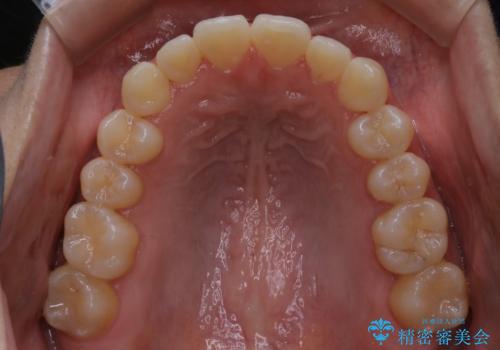

【非抜歯】部分矯正でも治る 前歯の反対咬合

- 前歯にガタつきを主訴にご来院されました。

奥歯の嚙み合わせに問題がほとんどみられなかったため、インビザライン ライトパッケージでの部分矯正を行うこととなりました。

今回のケースでは奥歯の噛み合わせに問題がほぼみられなかったため、前歯の位置のみに焦点を当て部分矯正を行いました。